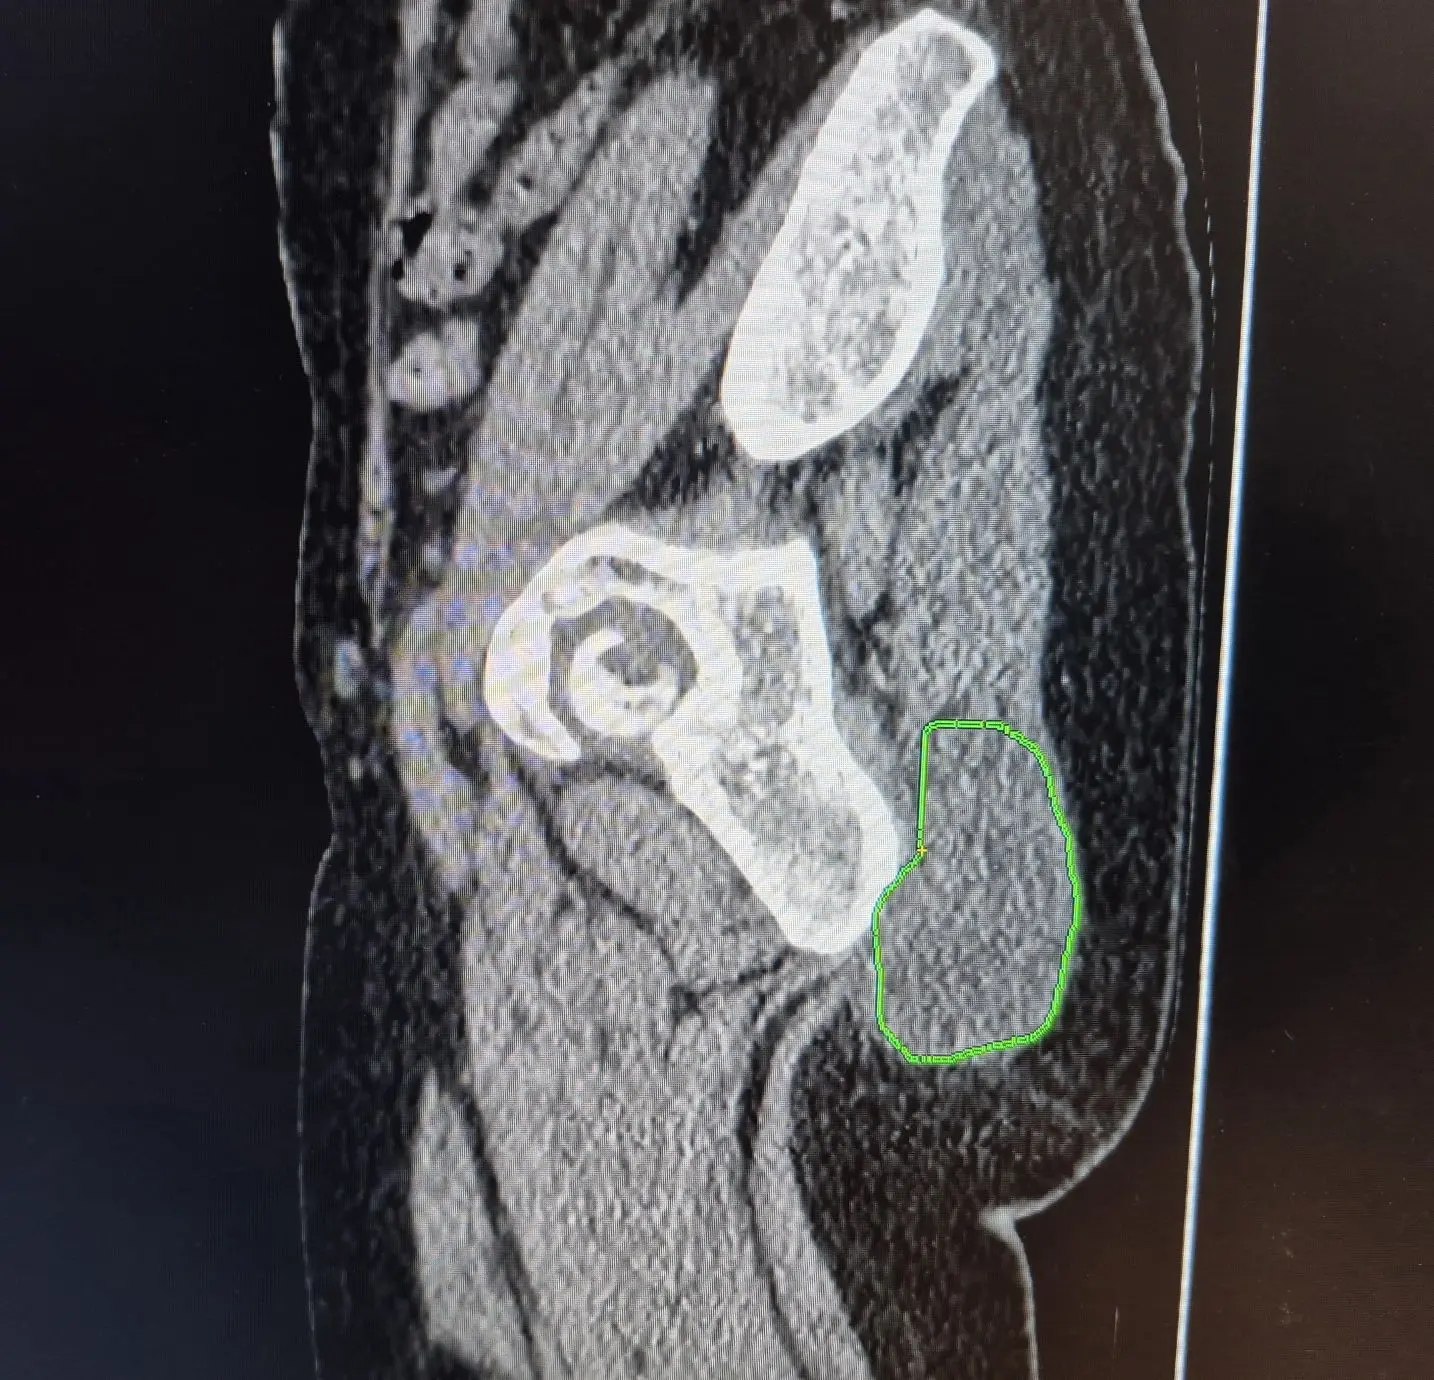

Клиническим случаем поделился заведующий хирургическим отделением Роман Тимохин. Пациентка обратилась в отделение с образованием в области ягодицы. Сначала опухоль была небольшой — около 1 см, но в течение нескольких месяцев начала расти.

Вместо того, чтобы воспользоваться помощью врачей, женщина отправилась на массаж. Массажист, приняв новообразование за обычный застой, попытался размять его мануальными техниками. После этого опухоль увеличиваться и достигла 10 см. Комплексное обследование в больнице показало, что жировик на деле оказался злокачественным новообразованием.

Пациентке сделали операцию. По словам специалистов, у неё есть все шансы на полное выздоровление.